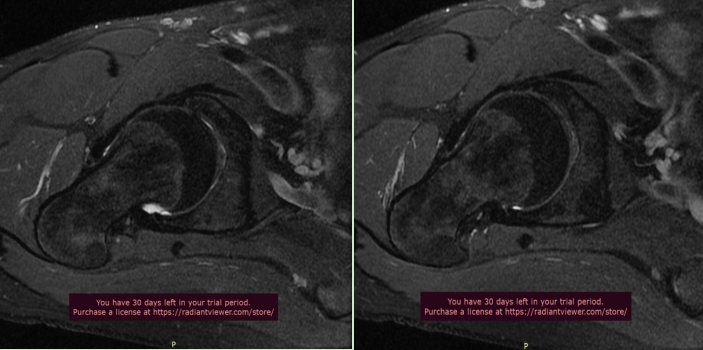

单髋关节一般采用小扫描视野,可以获得更好的信噪比及更高的空间分辨率图像,以及特殊扫描方位(斜冠状位、斜轴位),不但可以显示股骨头颈部病变情况,而且有利于髋臼及臼唇的显示。

下图为我科室扫描单髋关节图

单髋关节扫描对于诊断盂唇损伤和髋关节撞击综合征有非常重要的价值。临床医师如果考虑上述两种疾病,建议开单时选择单髋关节磁共振检查(高分辨率单髋关节扫描),扫描前请电话预约,窗口工作人员会告知您检查注意事项。